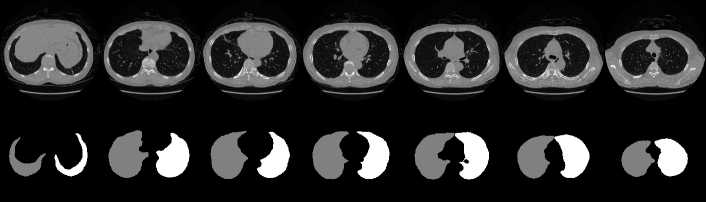

We used a publicly available pretrained lung segmentation network, U-net-R231 [29], to segment lung regions from each 3D stack of CT slices. We used the COVID-19 dataset [36] to evaluate the lung segmentation performance. The intersection of the ground truth for the 3D lung region with the U-net-R231 prediction was evaluated using the intersection over union (IoU) and Dice score and averaged across slices and stacks, obtaining the results listed in Table B. Compared with the performance evaluation results using the datasets in [29] (i.e., lung tissue research consortium––LTRC [37], lung CT segmentation challenge 2017––LCTSC [38], and vessel segmentation in the lung 2012––VESSEL12 [39]) also shown in Table B, U-net-R231 provides a high Dice score, thereby validating its excellent lung segmentation ability. Fig. F shows results of lung segmentation by U-net-R231 to illustrate its excellent performance.